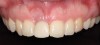

The patient was brought back weekly for 4 weeks for postoperative follow-up. Healing was satisfactory (Figure 18). Four months after implant placement, the final restoration, a porcelain-fused-to-metal screw-retained crown, was inserted at site No. 8 (Figure 19).

Fig 19. Final screw-retained crown on implant at site No. 8.

Figure 19